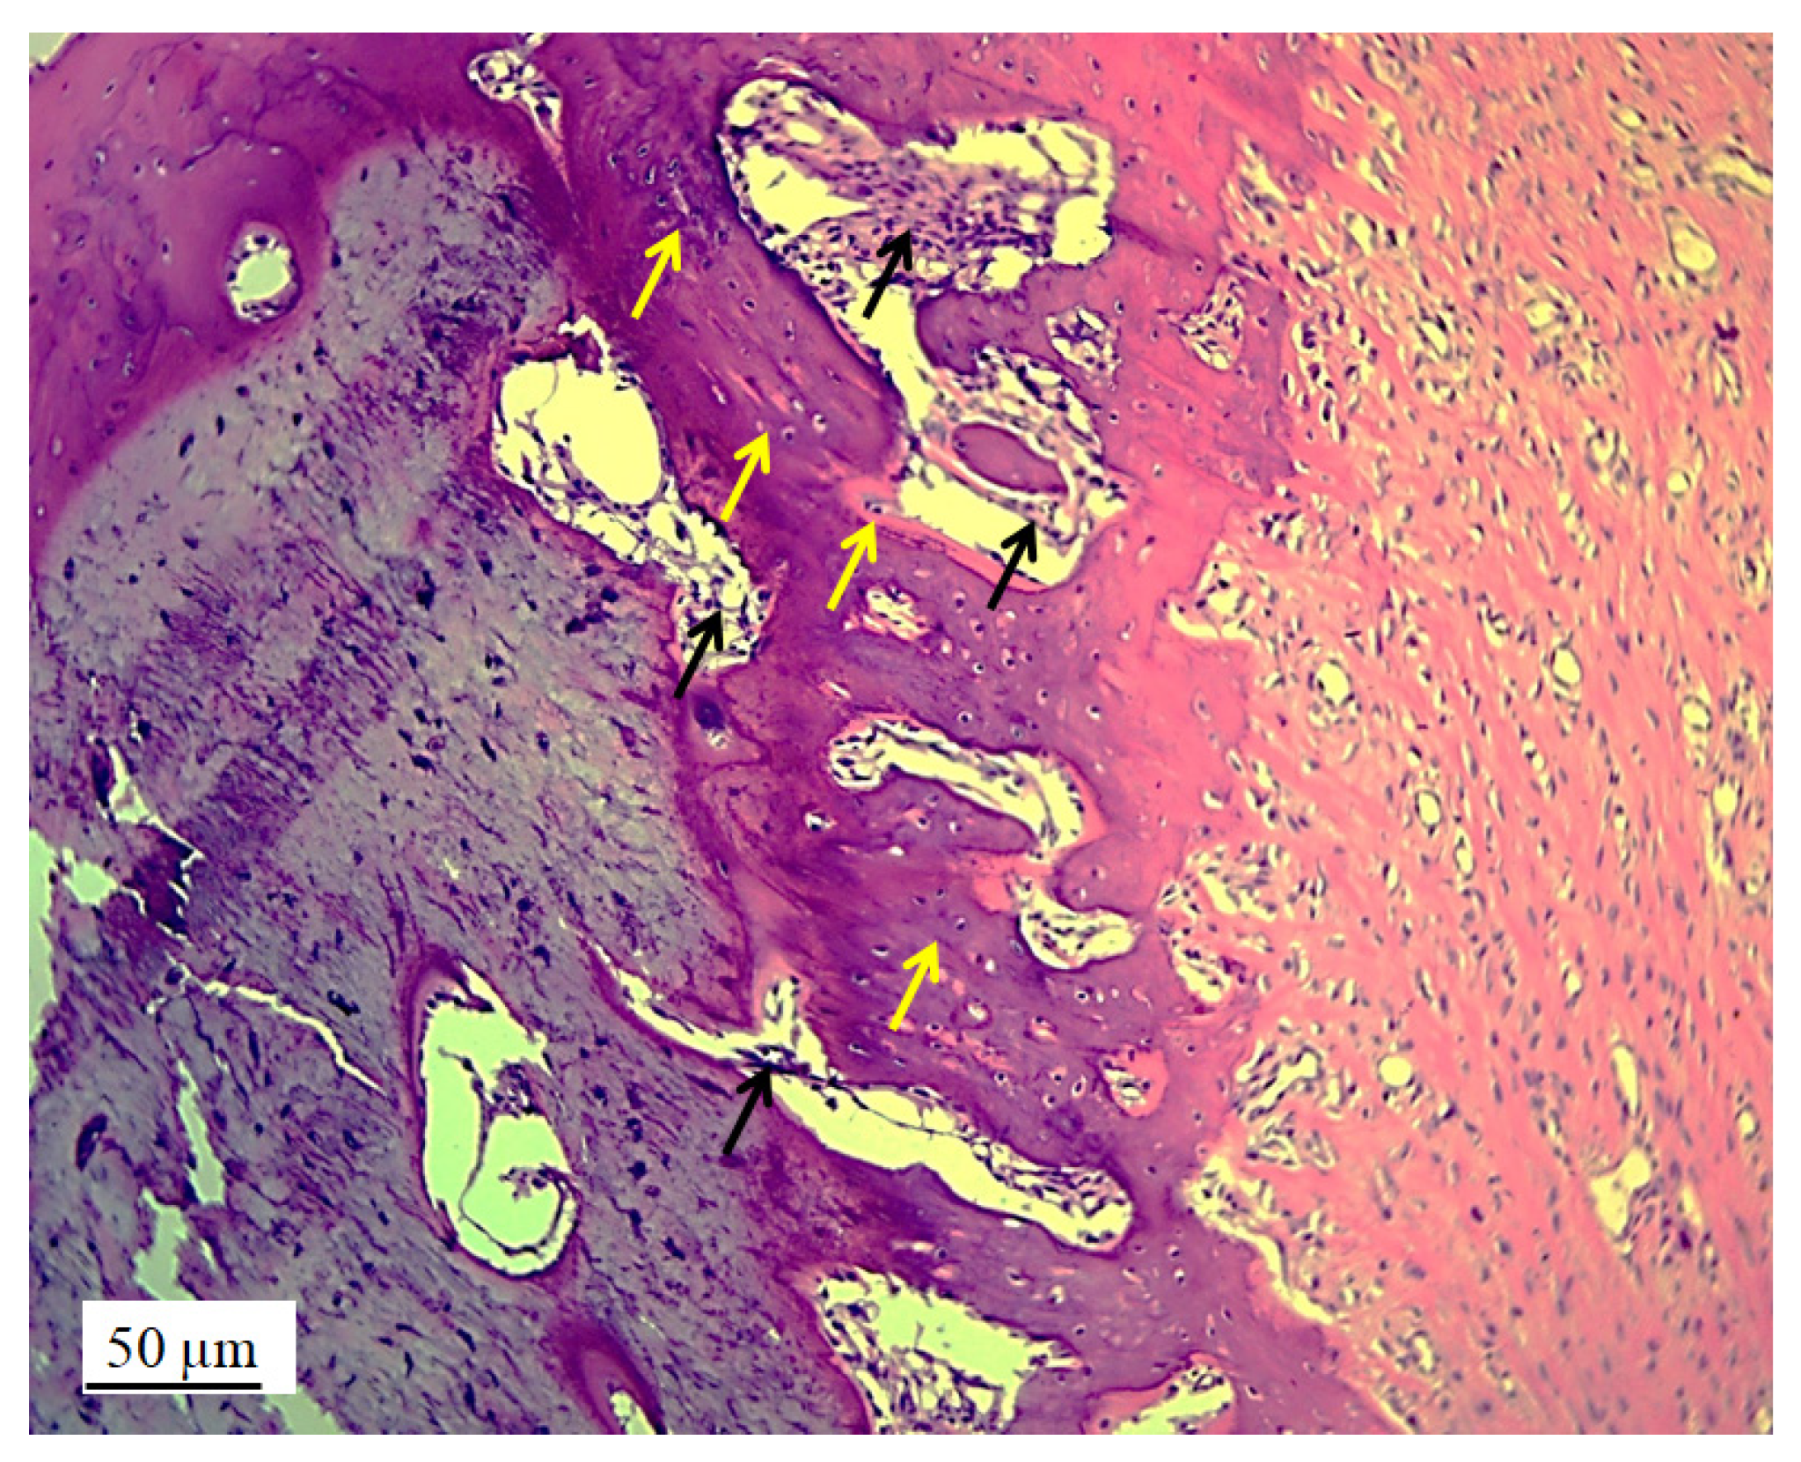

3.2.2. Bone Tissue in the Rabbit Joint Defect Region (Sub-Cartilage Region)

| Volume density of osteocytes (mm0) | 0.266 ± 0.019 ** | 0.225 ± 0.017 |

| Volume density of bone matrix (mm0) | 0.560 ± 0.044 *** | 0.447 ± 0.041 |

| Volume density of blood vessels in bone tissue (mm0) | 0.174 ± 0.015 | 0.328 ± 0.024 **** |

| Number of osteocytes | 28574.2 ± 2314.6 **** | 21759.1 ± 2219.4 |

| Numerical density of osteocytes (mm−3) | 3015.6 ± 353.3 * | 2554.5 ± 311.1 |

| Surface area of osteocytes (μm2) | 172.6 ± 15.4 *** | 139.3 ± 13.2 |

| Surface area of osteocytes nuclei (μm2) | 69.4 ± 8.4 | 60.5 ± 8.2 |

| Nucleocytoplasmic ratio (NCR) of osteocytes | 0.325 ± 0.031 | 0.409 ± 0.038 *** |

| Diameter of blood vessels (µm) | 55.5 ± 6.6 | 68.4 ± 7.2 ** |